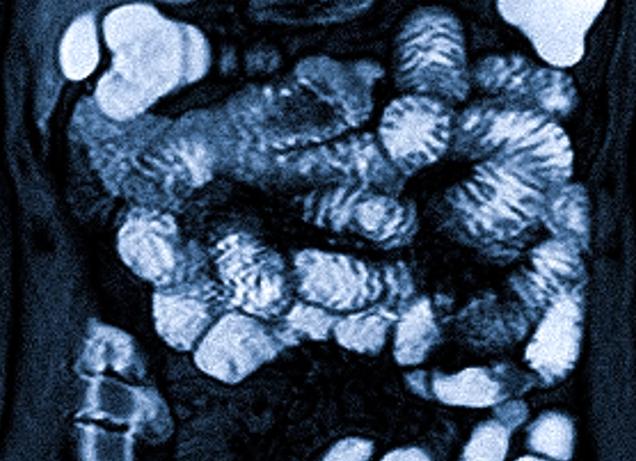

Сейчас же технологии ушли далеко вперед, и появился метод, благодаря которому можно в подробностях рассмотреть организм человека на экране – в цвете, объеме, с разных сторон и даже в «нарезке». Его название — магнитно-резонансная томография (МРТ).

80% организма человека — вода, молекула которой содержит два атома водорода. При сильнейшем воздействии магнитного поля они излучают волны разной длины — она зависит от диагностируемой области. Это отражается на цветном трехмерном изображении.

Проводя исследования желудочно-кишечного тракта с использованием МРТ кишечника, можно получить трехмерные изображения, которые отражают наличие опухолевых образований, их форму, объем и положение. Но не все мелкие патологии можно увидеть благодаря этому способу, так как из-за перистальтики кишечника информация может быть ложной, а изображение — нечетким. В таких ситуациях лучше провести дополнительное обследование.

На снимке МРТ возможно отразить даже самые недоступные части кишечника. Если пациент жалуется на боль в нескольких областях, диагностируется состояние нескольких отделов. Чаще всего это делается при подозрении на онкологическое заболевание.

Когда платформа продвигается вперед в аппарат, проводится серия последовательных снимков. В это время пациенту нужно задержать дыхание. Во время процедуры кольцо, создающее снимки, вращается, в результате чего активируется магнитное поле. Таким образом создаются «слоистые» изображения, которые позволяют в подробностях узнать о состоянии кишечника.